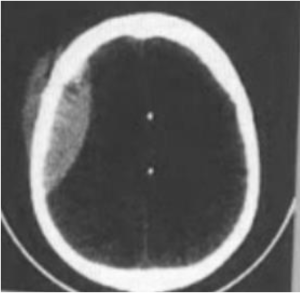

Klinis: KLL, benturan pada kepala dengan disertai pingsan dan muntah-muntah. Tampak lesi hiperdens pada daerah yang tampak di bawah ini. Diagnosis CT kepala

Klinis head injury (HI). Hasil CT scan kepala seperti di samping. Diagnosisnya adalah